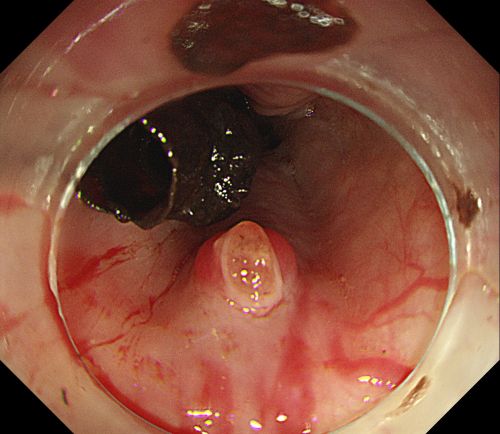

内镜下可见重度食管静脉曲张,且有较多血凝块。

内镜下胃底可见大量血液及血凝块。

彭娅主任在内镜下小心翼翼抽吸血液清洗血块后,找到“犯罪血管”。

患者旋即被推入手术室,麻醉三科刘际童主任为其进行气管插管、全麻,保持呼吸道通畅,并进行中心静脉置管等维持血压平稳。综合内科彭娅主任进行胃镜治疗,发现患者重度食管静脉曲张,胃底可见大量血液及血凝块;小心翼翼抽吸血液及清洗血块后,寻找到“犯罪血管”,在内镜下进行食管静脉曲张套扎+硬化剂注射治疗,封闭出血血管。